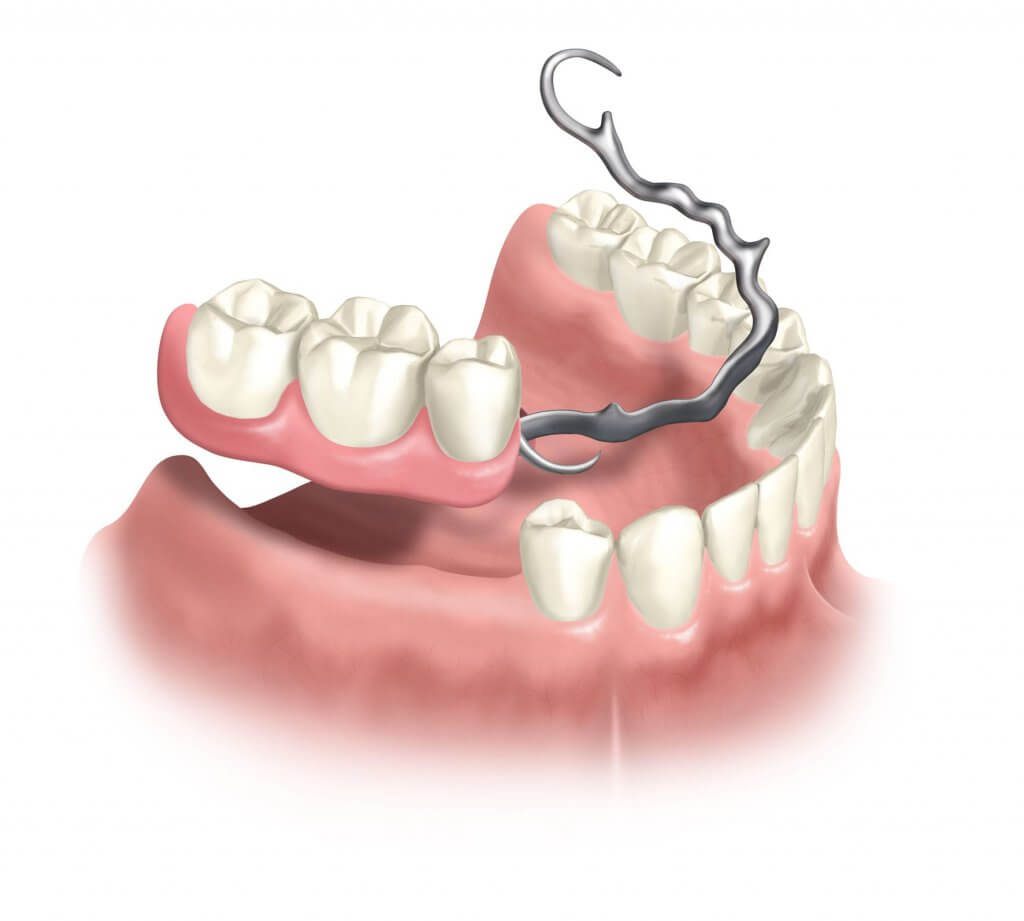

Современные методы протезирования зубов: Рекомендации и советы